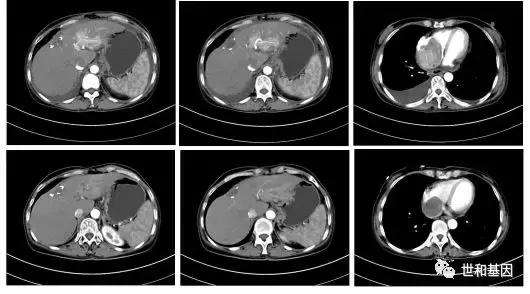

- 2019年6月,“帕博利珠单抗200mg+仑伐替尼8mg po qd”联合治疗。患者一般状况明显好转,无咯血、呕血,食纳睡眠可,体腹平软,肝脏肋下未及。两周期后复查CT提示肝脏病灶及右心房癌栓明显缩小,评估疗效PR。

上:治疗前CT(2019-06-26)

下:治疗后CT(2019-08-13)肝脏病灶及右心房癌栓明显缩小